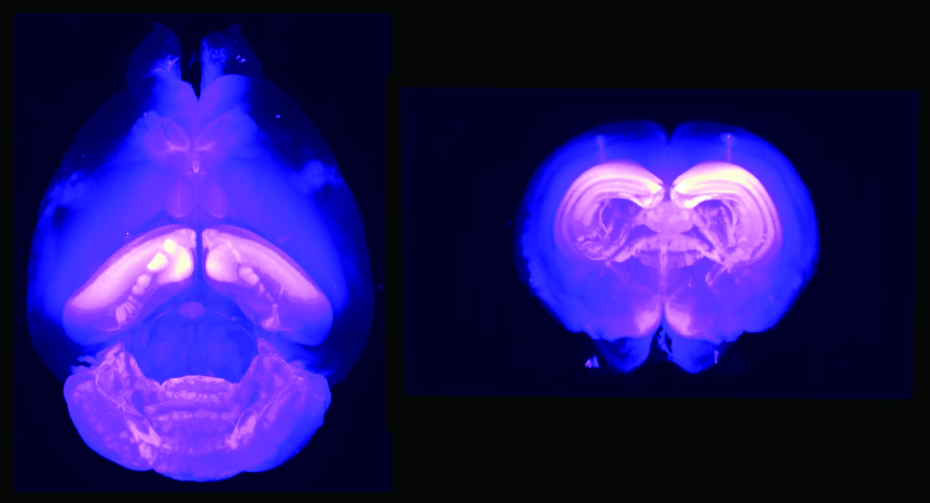

生きたマウス脳内の内在性AMPARのラベル化。

ラベル化受容体の全脳3Dイメージング。標識した受容体について、CUBICという方法で脳全体の3Dイメージングを行うことに成功した。 今後、例えば脳機能の調整に関係している特定の酵素の活性など、特定の知りたい対象について、脳全体で可視化することを目指している。また、開発したこの方法であれば、リガンドを変えることによって、AMPA受容体以外の様々な脳の受容体タンパク質を標識することができる。

透明化した脳。開発した方法によって蛍光色素で受容体を標識している。ライトで照らすと、標識した受容体は肉眼では捉えられない色のため見えないが、別の方法で染色した細胞の核が光って見える。